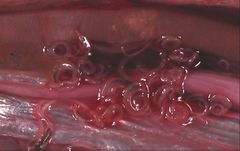

- The Anisakidae are also called the "marine mammal ascarids". The larvae of these worms cause anisakiasis when ingested by humans in raw or insufficiently cooked fish, but do not reproduce in humans.